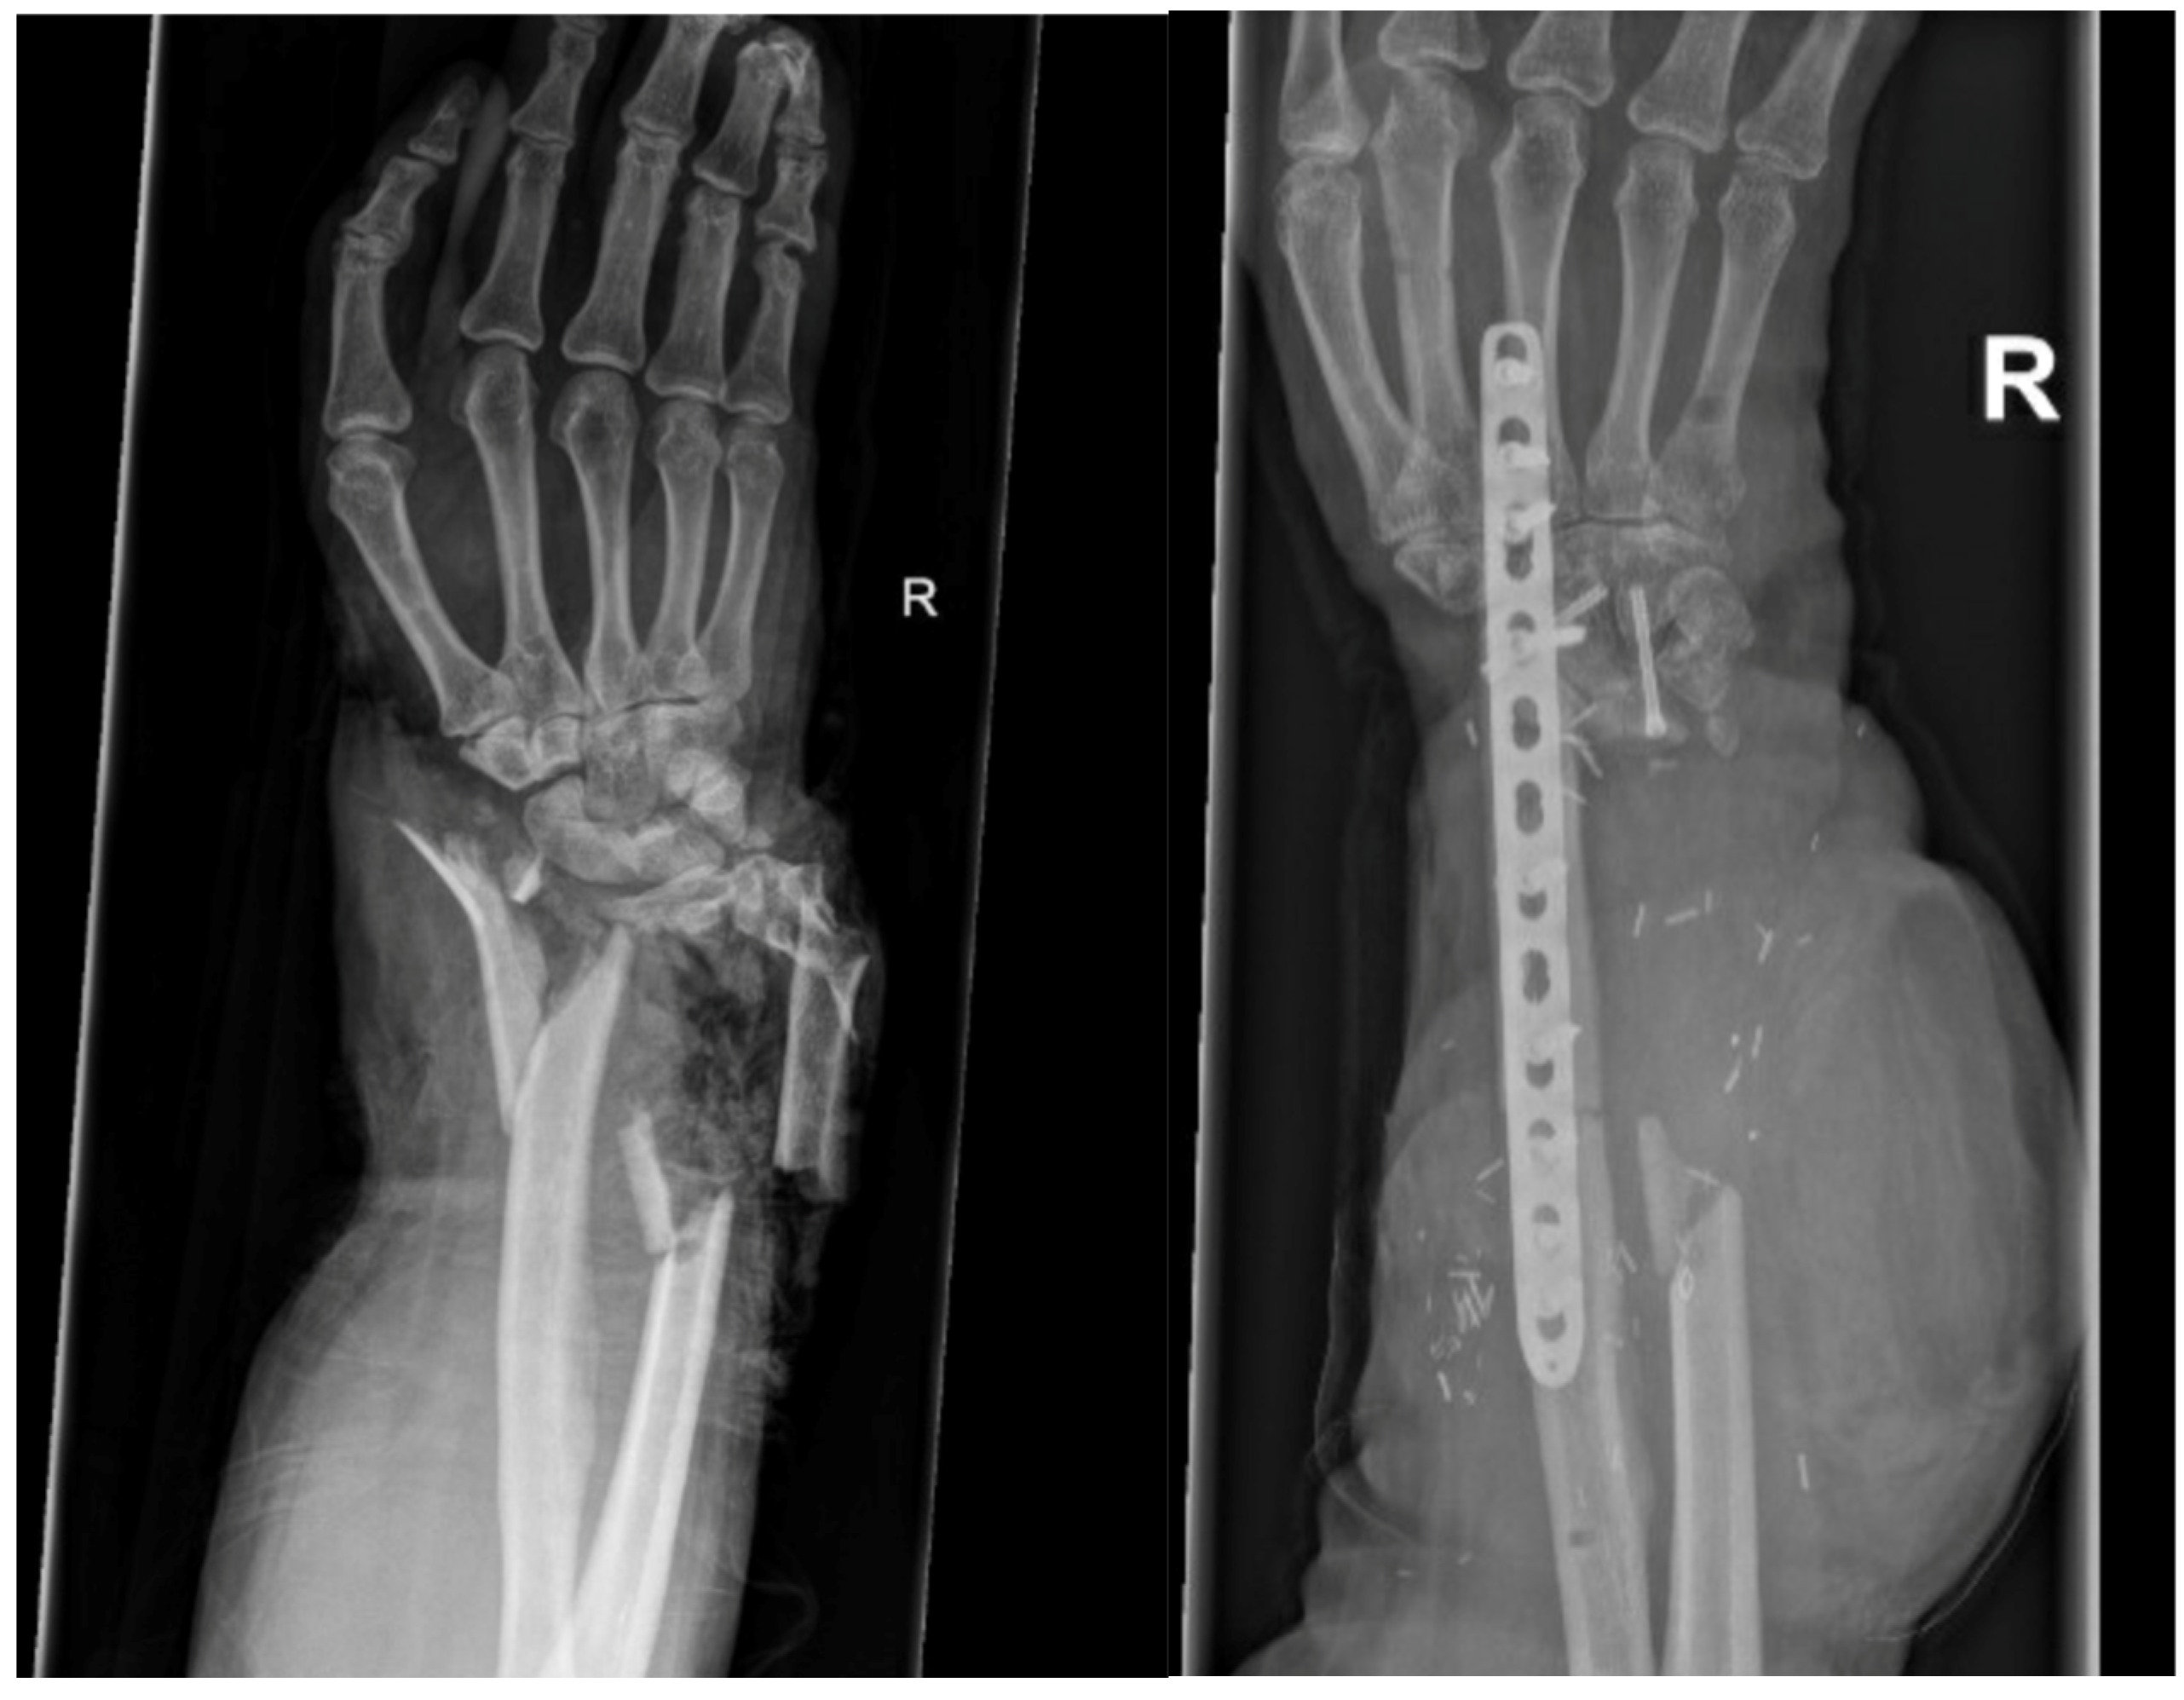

3.2.2. Arthrodesis of the Distal Radius and Middle Hand Using a Triangular-Shaped Vascularized Osteocutaneous Fibula Flap

| Case 3 | Complete wrist, distal radius and proximal metacarpals | Benign, aggressive bone tumor | 53 | 41 | 8 cm | Vascularized osteocutaneous triangular fibula | Wrist arthrodesis | N/A N/A | 0-0-0° 80-0-40° | 70% | MMWS = 45 DASH = 30 | yes | |